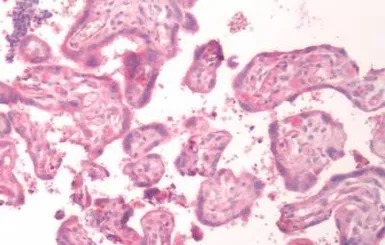

IHC-P analysis of human placenta tissue using GTX70845 Bradykinin B1 receptor antibody.